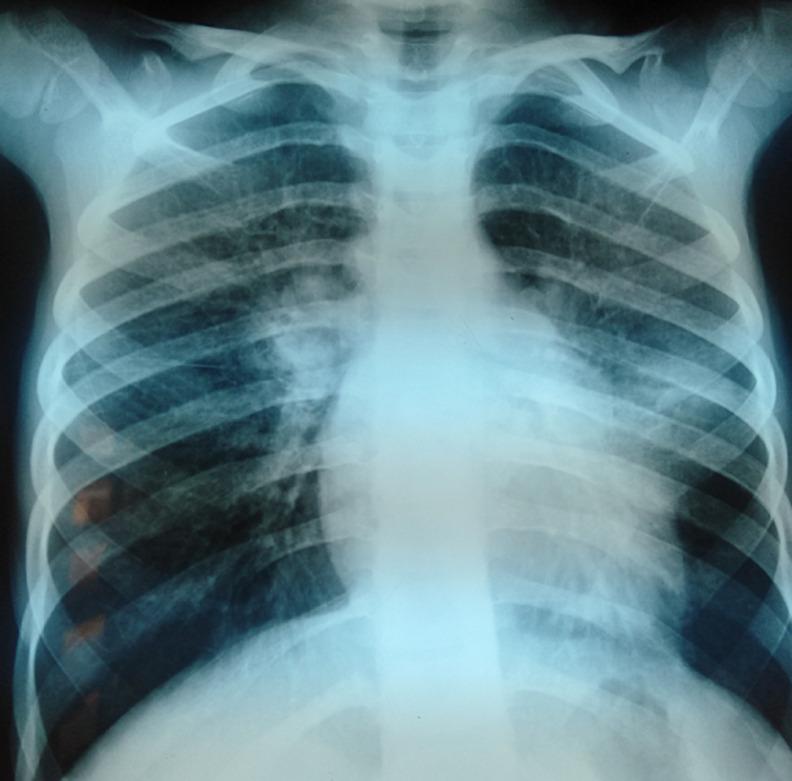

Bird fancier's disease falls within the spectrum of hypersensitivity pneumonitis secondary to immuno-allergic reaction to avian antigens. This occurs only rarely in children. It is found in two-thirds of patients with hypersensitivity pneumonitis. Diagnosis is not so easy. It is based on a body of clinical evidence. We here report the peculiar case of a 7-year-old girl with a family history of atopic disease initially treated as asthma based on the presence of wheezing and dyspnea and cough without improvement. The patient had worsening of symptoms such as dyspnea at rest complicated by cyanosis in respiratory distress. All of this took place in a context of alteration of general state. Clinical examination showed growth retardation, perioral cyanosis with digital hippocratism. Lung auscultation revealed bilateral crackling sounds. Chest X-ray objectified bilateral interstitial syndrome. Chest computed tomography (CT) scan showed diffuse ground-glass opacities. Laboratory tests revealed hypereosinophilia with hyper-IgE and excluded tuberculosis, cystic fibrosis, immune deficiency. In a second stage interview contact with birds was reported. Serological tests for bird fancier's disease were positive. The patient received inhaled corticosteroids associated with avoidance of exposure to birds. After a follow-up of 2 months, outcome was favorable. Given that the signs of bird fancier's disease are non-specific, this should be suspected in patients with respiratory symptoms associated with exposure to avian antigens.

养鸟人肺疾病属于对禽类抗原免疫过敏反应继发的超敏性肺炎范畴。这种疾病在儿童中极为罕见。在三分之二的超敏性肺炎患者中可发现此病。诊断并非易事,它基于一系列临床证据。我们在此报告一例特殊病例,一名7岁女孩,有特应性疾病家族史,最初因喘息、呼吸困难和咳嗽被诊断为哮喘,但治疗后未见改善。患者出现如静息时呼吸困难加重并伴有呼吸窘迫时发绀等症状恶化情况。所有这些均发生在全身状况改变的背景下。临床检查显示生长发育迟缓、口周发绀伴杵状指。肺部听诊发现双侧有啰音。胸部X线检查显示双侧间质性综合征。胸部计算机断层扫描(CT)显示弥漫性磨玻璃样混浊。实验室检查显示嗜酸性粒细胞增多伴IgE升高,并排除了结核病、囊性纤维化和免疫缺陷。在第二阶段访谈中,患者报告曾接触鸟类。养鸟人肺疾病的血清学检查呈阳性。患者接受了吸入性糖皮质激素治疗,并避免接触鸟类。经过2个月的随访,结果良好。鉴于养鸟人肺疾病的症状不具有特异性,对于有接触禽类抗原相关呼吸道症状的患者应怀疑此病。